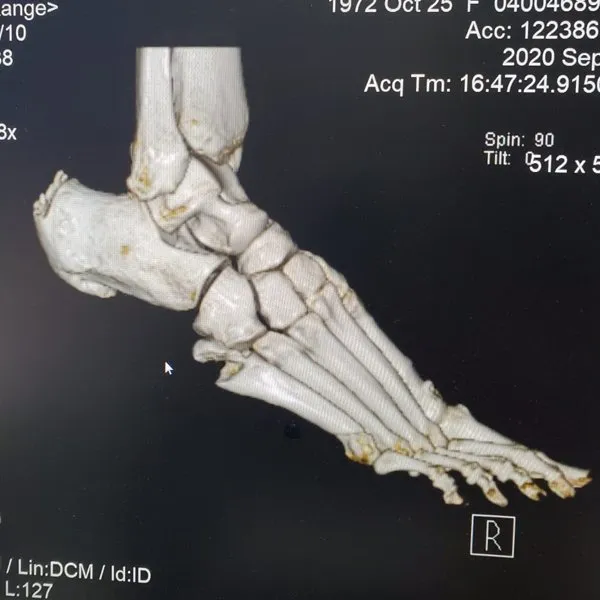

See What's Going on Inside Our Podiatrist's Office

With 32 years of experience, Dr. Daniel Brandwein DPM, PA, FACFAS is your trusted choice for podiatric care in the Pompano Beach, FL area. Take a look at the photos below to see what's happening inside our locally and family owned clinic. To find out how we can help with your foot care needs, please contact us today.